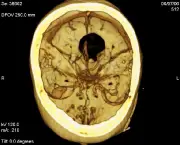

O Aneurisma Cerebral pode ser definido basicamente como uma dilatação anormal de uma das artérias do cérebro. Essa dilatação pode levar a ruptura dessa artéria, o que gera sangramentos que seguem para um espaço do cérebro chamado de “espaço subaracnóide”.